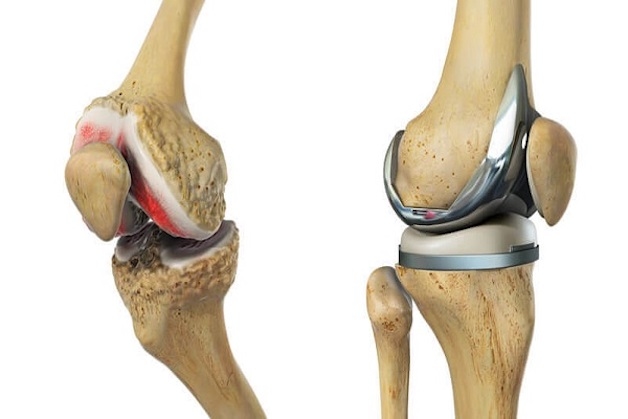

Cùng với sự tiến bộ của nền y học và kỹ thuật, sự ra đời của khớp gối nhân tạo đã mang tới hy vọng mới cho các bệnh nhân bị thoái hóa khớp gối. Phương pháp phẫu thuật thay khớp gối nhân tạo sẽ giúp điều trị tận gốc bệnh thoái hóa khớp gối bằng cách thay thế một khớp gối nhân tạo mới để giúp cho bệnh nhân phục hồi khả năng vận động của khớp gối và trở về đời sống sinh hoạt bình thường.

Phẫu thuật thay khớp gối được chỉ định cho đối với những trường hợp bị thoái hóa khớp gối nặng, sụn khớp bị ăn mòn, lệch trục chân nghiêm trọng hoặc bệnh viêm khớp dạng thấp gây phá hủy khớp mà việc tiến hánh điều trị nội khoa không thể khắc phục được.

Có hai loại phẫu thuật thay khớp gối nhân tạo đó là phương pháp thay khớp gối bán phần và thay khớp gối toàn phần. Việc bác sĩ lựa chọn loại khớp gối nhân tạo nào sẽ phụ thuộc vào tình trạng và nhu cầu của bệnh nhân.

1.2. Kỹ thuật thay khớp gối nhân tạo toàn phần

Thay khớp gối toàn phần thường được chỉ định với các trường hợp bị viêm hoặc thoái hóa khớp một cách nghiêm trọng. Với trường hợp này thì toàn bộ phần khớp gối sẽ được thay thế bằng các vật liệu nhân tạo.